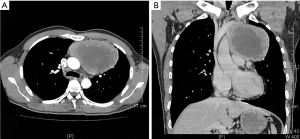

On January 15th in 2019, a 42-year-old male was referred to our hospital, complaining of chest pain and tightness for over 1 month, and the symptoms were getting worse gradually in the last week. He had no history of malignancy, and tumor family history, as well as genetic history, was not found. The patient reported no fever, cough, hemoptysis, difficulty swallowing, dyspnea, hoarseness and limb weakness. No positive signs were detected in routine physical examination and tumor markers were normal, such as carcino-embryonic antigen (CEA), ferritin (FER). Chest CT revealed a large left-anterior mediastinum mass. Further evaluation demonstrated a 115 mm × 95 mm mass with patchy necrosis, heterogeneous enhancement and small blood vessels. Moreover, the large mass compressed left brachiocephalic veins, pericardium and upper-lobe of left lung (Figure 1). Based on clinical and CT appearances, the patient was suspected of invasive thymoma or thymic carcinoma pre-operatively. Due to the estimated great-difficulty by video-assisted thoracoscopic surgery (VATS), median sternotomy was performed to remove the tumor in January 30th, 2019. During the surgery, we found that the tumor was located in the left-anterior mediastinum with incomplete capsule, and that part of upper-lobe of left lung was compressed by the large mass. Complete tumor resection with combined reginal mediastinal lymph node dissection were performed. Hematoxylin-eosin (HE) staining showed that the tumor cells were arranged in a nested, or ribbon pattern, with mild atypia, local hemorrhage, foci of necrosis and abundant interstitial blood vessels (Figure 2). Immunohistochemistry demonstrated positivity for CD56, Syn, CgA, CK (Figure 3A,B,C,D), and staining indices for Ki-67 was 15% (Figure 3E). No metastasis was found in all the 4 resected mediastinal lymph nodes. Postoperative pathology turned out to be primary TAC, Masaoka stage II (7). Postoperative chest CT (Figure 4A) showed that the tumor was resected completely and no recurrence occurred in postoperative follow-up (Figure 4B). From March 3rd on, a total of 6 cycles of postoperative adjuvant chemotherapy was given per 3 weeks successfully, and the chemotherapy regimen was gemcitabine (1,000 mg/m2 on 1st day) plus cisplatin (80 mg/m2 on 1st day). No 3/4 grade adverse effects (AEs) occurred during the perioperative period. There was no tumor recurrence or metastasis during the postoperative follow-up. A time lime showed the whole medical procedure of the special case (Figure 5).